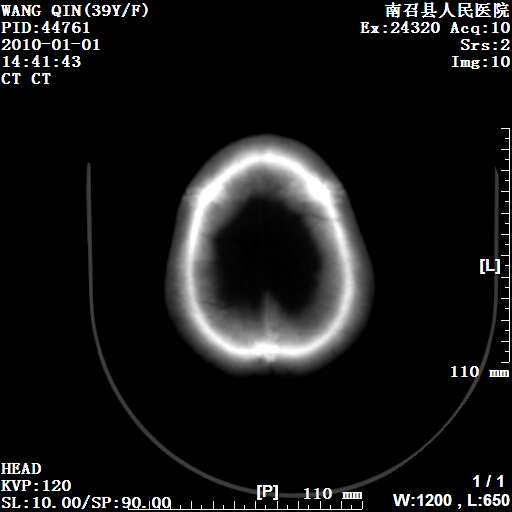

以下是引用随光逐影在2010-1-22 9:03:00的发言:[br]考虑左侧中颅窝(蝶骨翼区)脑膜瘤侵犯蝶骨翼并突入左侧眼眶。

以下是引用水过无痕在2010-1-22 14:55:00的发言:[br]一、定位:颅外占位;二、定性:恶性可能性大;三、组织来源:来源于左侧眼外直肌或其他部位;考虑为:横纹肌肉瘤>转移瘤>脑膜瘤.